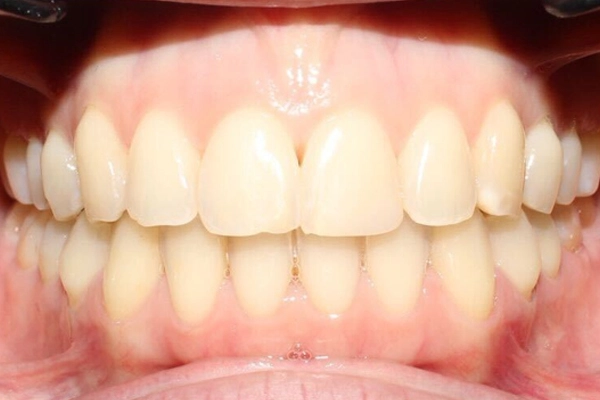

Conoce el antes y después de nuestros tratamientos